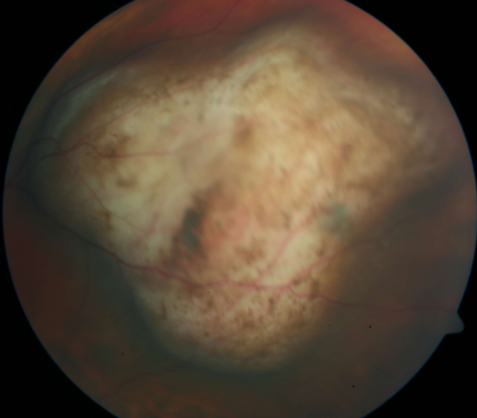

retinoblastoma

retinoblastoma

retinoblastoma